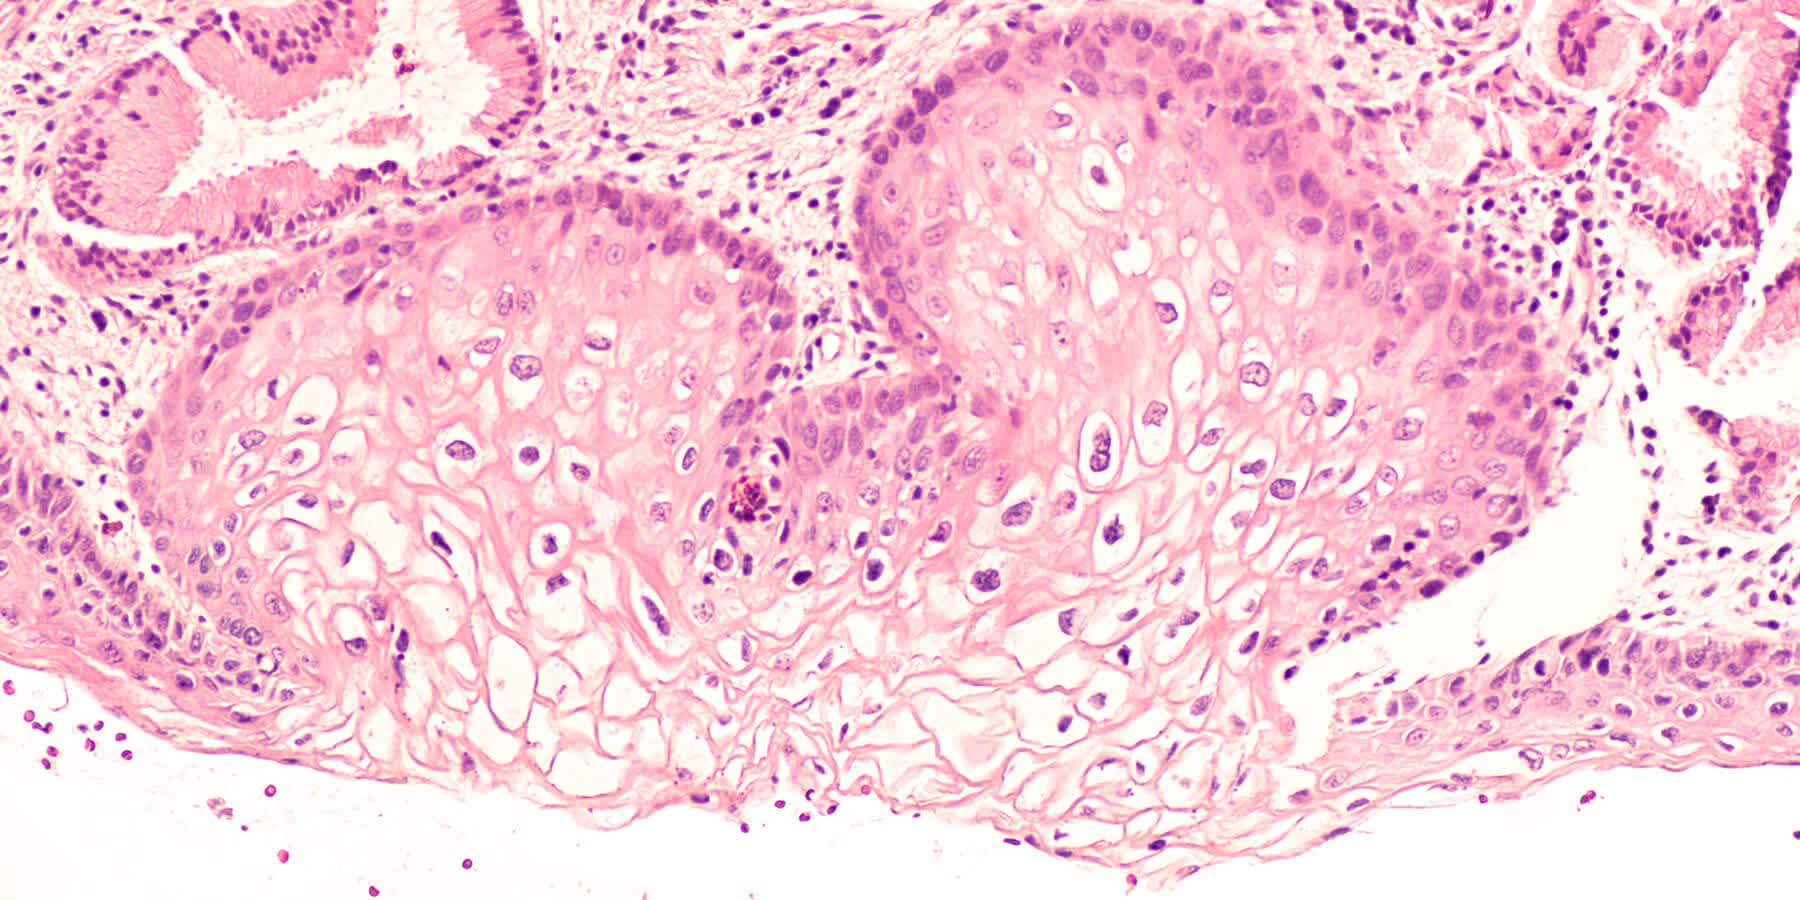

A Pap smear is a simple and effective screening test used to detect precancerous or cancerous cells in the cervix. It involves collecting cells from the cervix and examining them under a microscope to identify any abnormal changes that may indicate cervical cancer or other health issues.